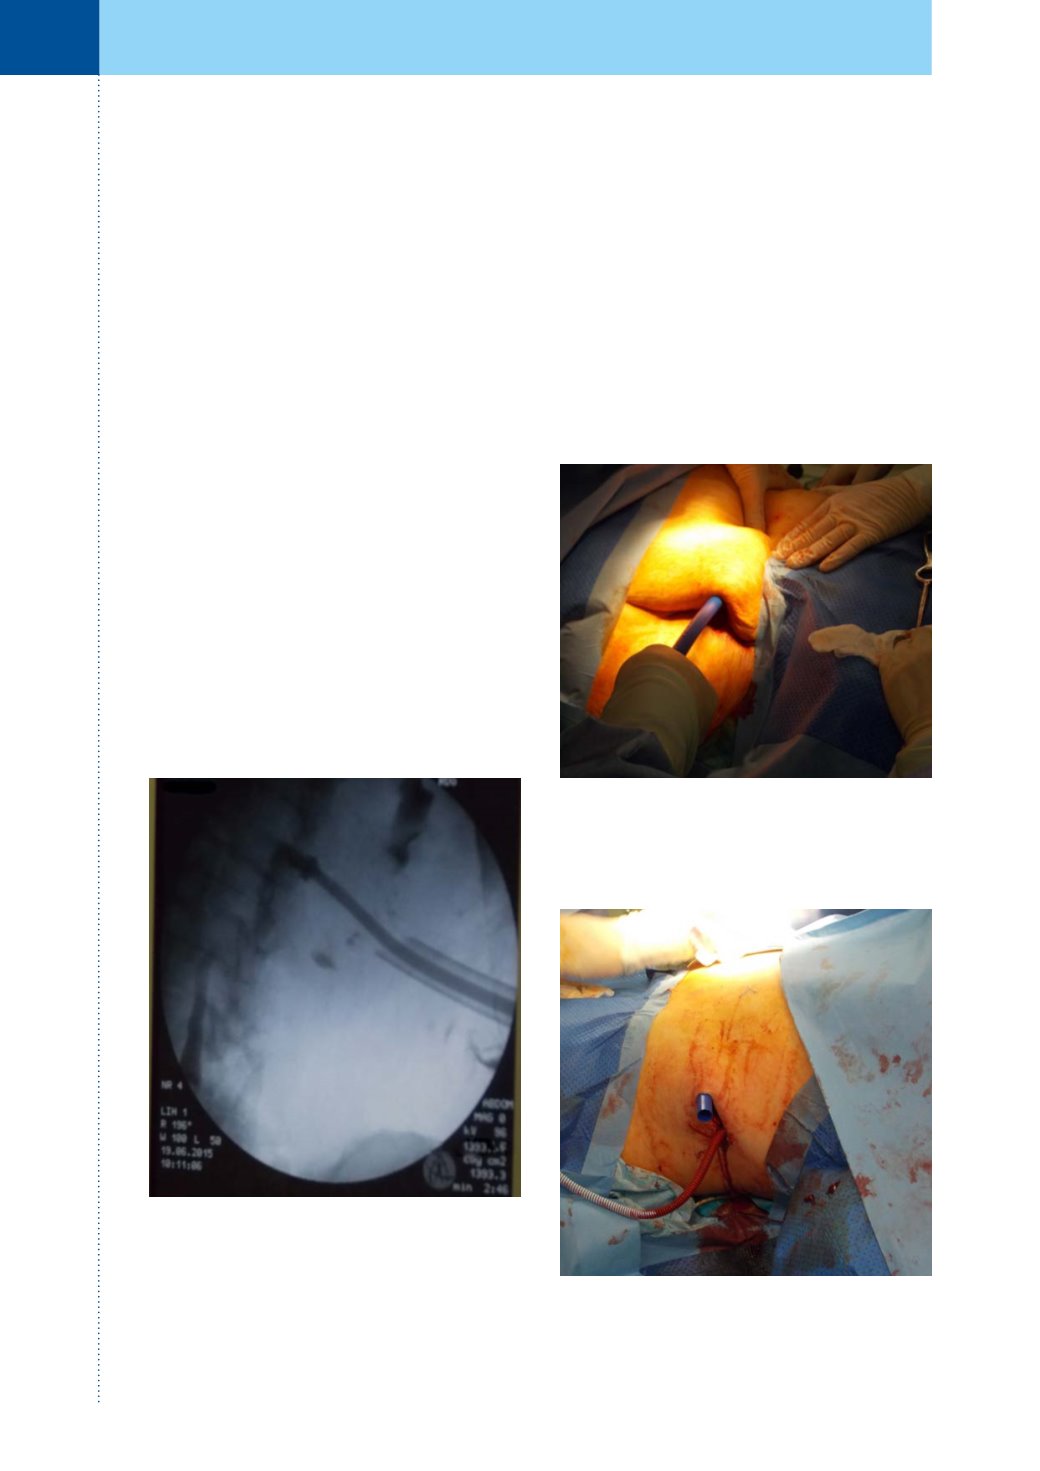

Zákrok byl proveden v celkové anestezii. Při za-

vádění byla využita již existující nefrostomie vle-

vo. Do ní jsme zavedli vodič, poté jsme vytáhli

nefrostomický drén a po zavedeném vodiči jsme

provedli dilataci kanálu na 30F. Pod rentgenovou

kontrolou jsme zavedli proximální konec extra-ana-

tomického stentu do ledvinové pánvičky. Správné

uložení proximálního konce stentu bylo možno

kontrolovat skiaskopicky, jelikož zakončení Detour©

extra-anatomického stentu je opatřeno speciálním

rentgen–kontrastním prstencem (obrázek 1).

Obr. 1.

Skiaskopická kontrola správného uložení

rentgen kontrastního prstence proximálního konce

stentu v ledvině

Obr. 3.

Příprava stentu k zavedení do tunelizátoru

Obr. 2.

Tunelizování podkoží speciálním tunelizá-

torem

V místě původního vpichu nefrostomie pro-

vedena kožní incize, další kožní incize provedena

v blízkosti vyústění ureteroileostomie (obrázek 5).

Přiloženým tunelizátorem byl vytvořen prostor

v podkoží pro střední goretexovou část stentu (ob-

rázky 2 a 3). Středem tunelizátoru protažen De-

tour© extra-anatomický stent (obrázek 4). Délka